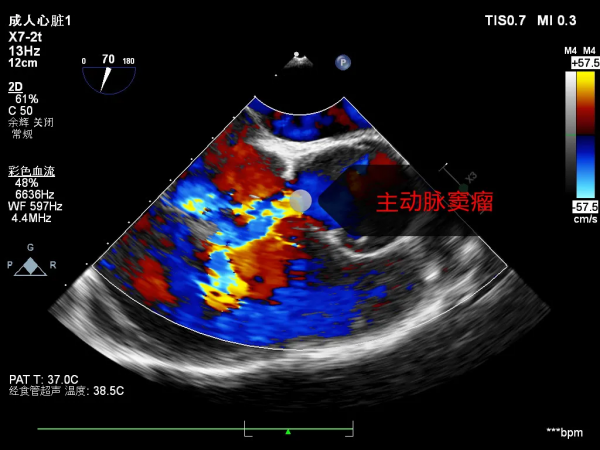

經河南省胸科醫院心血管外科八病區(大血管外科)主任張力診斷,小趙患有先天性的主動脈竇瘤,主動脈竇壁先天薄弱向外膨出瘤變,達到一定程度破入了心臟的右心房,破口逐漸增大,這也是造成小趙心功能不全,出現活動耐力下降、胸悶的主要原因!

竇瘤在異常血流的衝擊下造成心臟內膜損傷感染,三尖瓣和主動脈瓣葉被細菌侵蝕、潰爛穿孔,瓣膜重度關閉不全,導致小趙出現心衰。

術中探查發現:主動脈竇瘤破裂入右房衝擊三尖瓣,主動脈瓣一個瓣葉穿孔,三尖瓣前葉巨大穿孔,二尖瓣上也見到少量細菌感染的贅生物。因主動脈瓣及三尖瓣毀損嚴重,手術團隊決定更換為人造機械瓣膜,並去除了二尖瓣贅生物,瓣膜大部分組織尚好,修復成功。